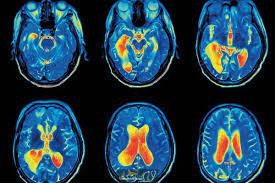

زمان طلایی برای درمان بیماران سکته مغزی و جلوگیری از عوارض، 3 تا 6 ساعت است

عضو هیأت علمی گروه مغز و اعصاب دانشگاه علوم پزشکی مشهد گفت: 3 تا 6 ساعت پس از سکته مغزی ، زمان طلایی برای حضور در بیمارستان و تزریق دارو و انجام اقدامات لختهبرداری تهاجمی محسوب می شود.